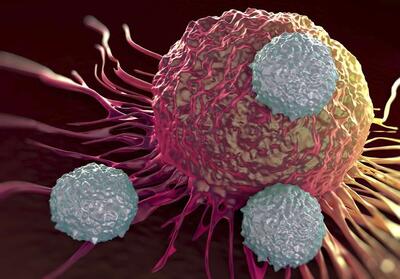

سالانه 9800 مورد جدید سرطان در فارس تشخیص داده میشود - تسنیم

کارشناس پیشگیری و کنترل سرطان معاونت بهداشت دانشگاه علوم پزشکی شیراز، گفت: سالانه 9800 مورد جدید سرطان در استان فارس تشخیص داده میشود.